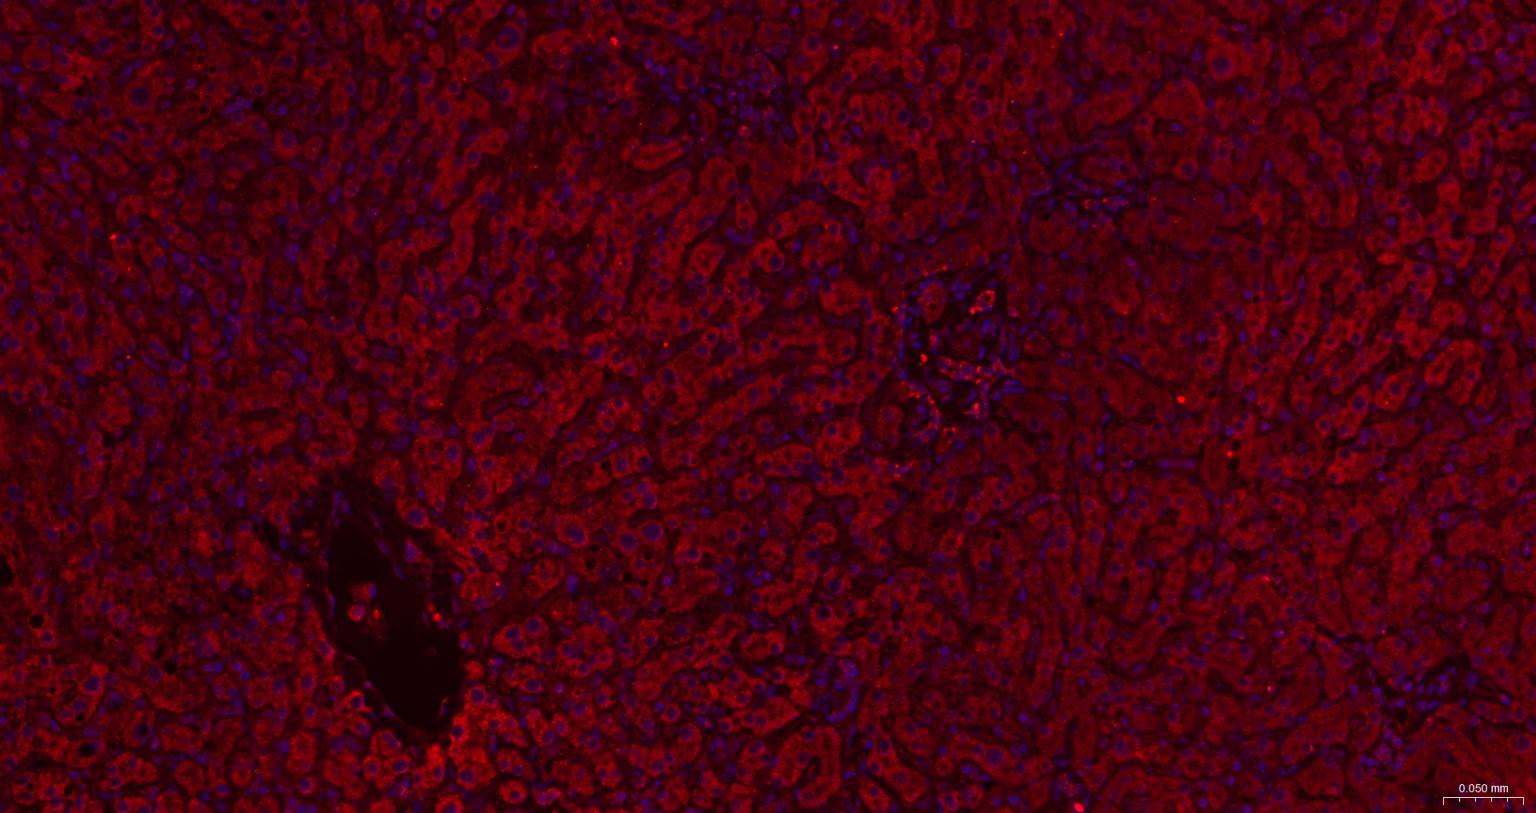

| IHC-P | Human, Mouse, Rat, Rabbit, Pig, Cow, Dog, Horse | 1:100-500 | |

| IHC-F | Human, Mouse, Rat, Rabbit, Pig, Cow, Dog, Horse | 1:100-500 | |

| IF | Human, Mouse, Rat | Rabbit, Pig, Cow, Dog, Horse | 1:100-500 |

交叉反应: Human, Mouse, Rat (predicted: Rabbit, Pig, Cow, Dog, Horse)